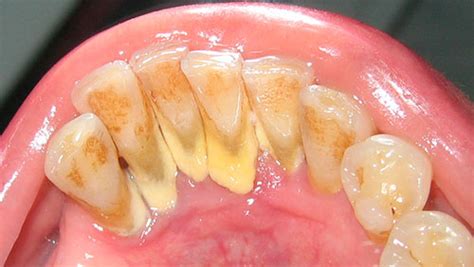

El sarro, también conocido como cálculo dental, es una acumulación endurecida de placa bacteriana que se forma en los dientes y puede dañar el esmalte dental y provocar caries. El sarro, a veces denominado cálculo o tártaro dental, es la placa que se ha endurecido en los dientes debido al depósito de minerales.

A diferencia de la placa que es una película incolora, el sarro presenta minerales siendo fácilmente visible si se localiza por encima de la línea de las encías. El indicador de sarro más común es observar un color marrón o amarillento en los dientes o encías. Al ser más poroso, absorbe fácilmente las manchas.

El sarro no sólo amenaza la salud de dientes y encías, también es un problema estético. También puede formarse por encima y por debajo de la línea de las encías y puede irritar el tejido gingival. Cuando no se erradica a tiempo, el sarro puede acumularse sobre y/o entre los dientes.